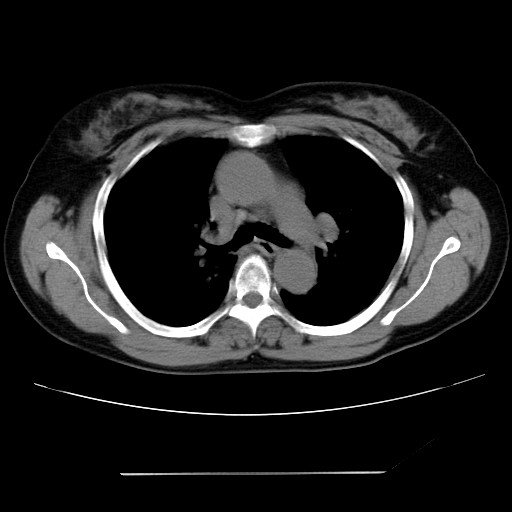

标题: CT24018:女性,62岁,咳嗽4年,无热,胸部CT扫 [打印本页]

女性,62岁,长期咳嗽,既往从事工作有粉尘接触,有高血压病史,110/150mmhg,近日咳嗽加重,脸面浮肿,请大家帮看下,

1、尘肺;2、慢性支气管炎合并肺部感染;3、心影增大(左房、左室大),考虑高血压性心脏病。

慢支并肺部炎症;右肺结核球?主肺动脉、右肺动脉影不宽,右心室不大,不支持肺心病;无心包积液。

1)慢性支气管炎并肺部感染、肺气肿。2)肺间质纤维化。